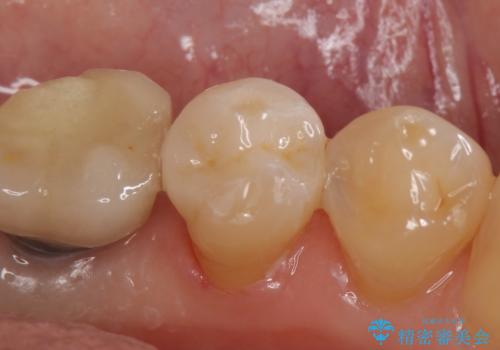

- 左下5番目の銀歯が気になるのでセラミックにしたいといらっしゃった方の症例です。

銀歯及び虫歯を除去後、セラミックインレーによる修復を行いました。

当院のセラミックインレーはemaxという強度と審美性に優れた材料を使用しています。

またプレス方式でインレーを製作しているため、削り出しで製作するCADCAMより優れた適合性も持ち合わせており、虫歯が再発しにくい修復物です。